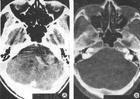

(2)CT及MRI扫描:CT表现为瘤体呈等密度或低密度,少数呈高密度影像。肿瘤多为圆形或不规则形,位于内听道口区,增强效应明显。MRIT1加权像上呈略低或等信号,在T2加权像上呈高信号。第四脑室受压变形,脑干及小脑亦变形移位。注射造影剂后瘤实质部分明显均一强化,囊变区不强化。

(3)CT及MRI检查:目前听神经鞘瘤诊断的标准是Gd-DTDA增强的MRI,特别是当肿瘤很小(<1cm)或在内听道内,CT扫描阴性又高度怀疑肿瘤存在时应该进行GD-DTPA增强的MRI。CT与MRI两种检查有相辅相成的作用,如CT发现有病侧内听道扩大时,增强CT可发现肿瘤对于估计中颅窝入路时颞骨的气化程度及高颈静脉球与后半规管及底的距离有帮助。如果病人已作了CT而肿瘤较大,MRI可提供对脑干压迫的范围Ⅳ脑室是否通畅脑积水、是否存在的情况对可疑听神经鞘瘤或CT检查难于确定时,全序列的MRI可做出鉴别诊断。但也要注意Gd-DTPA的可能假阳性,这与内听道内神经的炎症或蛛网膜炎有关;任何小的接近底部的增强病变应该在六月后作MRI复查,以评估其生长情况。